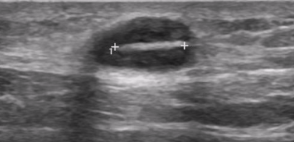

Intermediate phase of foreign body

Foreign body present 3 - 10 days

Fluid replaces air

Most pronounced hypoechoic halo